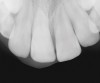

Figure 6  Root resorption secondary to orthodontic tooth movement.

Figure 6